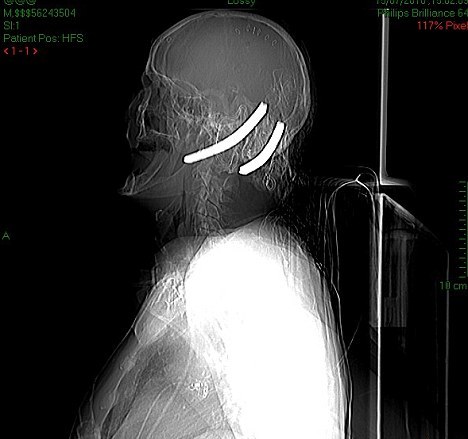

Ο Hugh έπεσε λιπόθυμος στο πάτωμα μέσα σε μια λίμνη αίματος. Τον βρήκαν την επόμενη μέρα και όταν μεταφέρθηκε στο νοσοκομείο οι γιατροί αναγκάστηκαν να καλέσουν την πυροσβεστική για να κόψουν με ειδικά εργαλεία τα «δόντια» που «περίσσευαν», ενώ είχαν προειδοποιήσει την οικογένειά του ότι δε θα άντεχε περισσότερες από 24 ώρες.

Επί τρεις μήνες ήταν σε κώμα και πάλευε για τη ζωή του και τελικά τα κατάφερε. Όμως η ζωή του ποτέ δε θα είναι ξανά φυσιολογική, καθώς χρειάζεται καθημερινή φροντίδα από ειδικό νοσηλευτή, λόγω των βαρύτατων εγκεφαλικών κακώσεων που υπέστη ενώ έχει χάσει και την ικανότητα της ομιλίας.